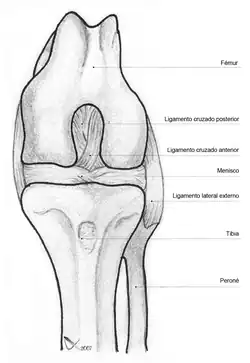

La rodilla está sustentada por fuertes ligamentos que impiden que sufra una luxación, siendo los más importantes el ligamento lateral externo, el ligamento lateral interno, el ligamento cruzado anterior y el ligamento cruzado posterior.[4]

Ligamentos

La rodilla esta sustentada por varios ligamentos que le dan estabilidad y evitan movimientos excesivos. Los ligamentos que están en el interior de la cápsula articular se llaman intraarticulares o intracapsulares, entre los que se encuentra el ligamento cruzado anterior y el ligamento cruzado posterior. Por otra parte los ligamentos que están por fuera de la cápsula articular se llaman extrarticulares o extracapsulares como el ligamento lateral interno y el ligamento lateral externo.[8][9]

Intraarticulares

- Ligamento cruzado anterior (LCA).

- Ligamento cruzado posterior (LCP).

- Ligamento yugal o ligamento transverso. Une los meniscos por su lado anterior.

- Ligamento meniscofemoral anterior o Ligamento de Humphrey. Del menisco externo al cóndilo interno del fémur.[10]

- Ligamento meniscofemoral posterior o Ligamento de Wrisberg. Del menisco externo al cóndilo interno del fémur, por detrás del meniscofemoral anterior.[11]